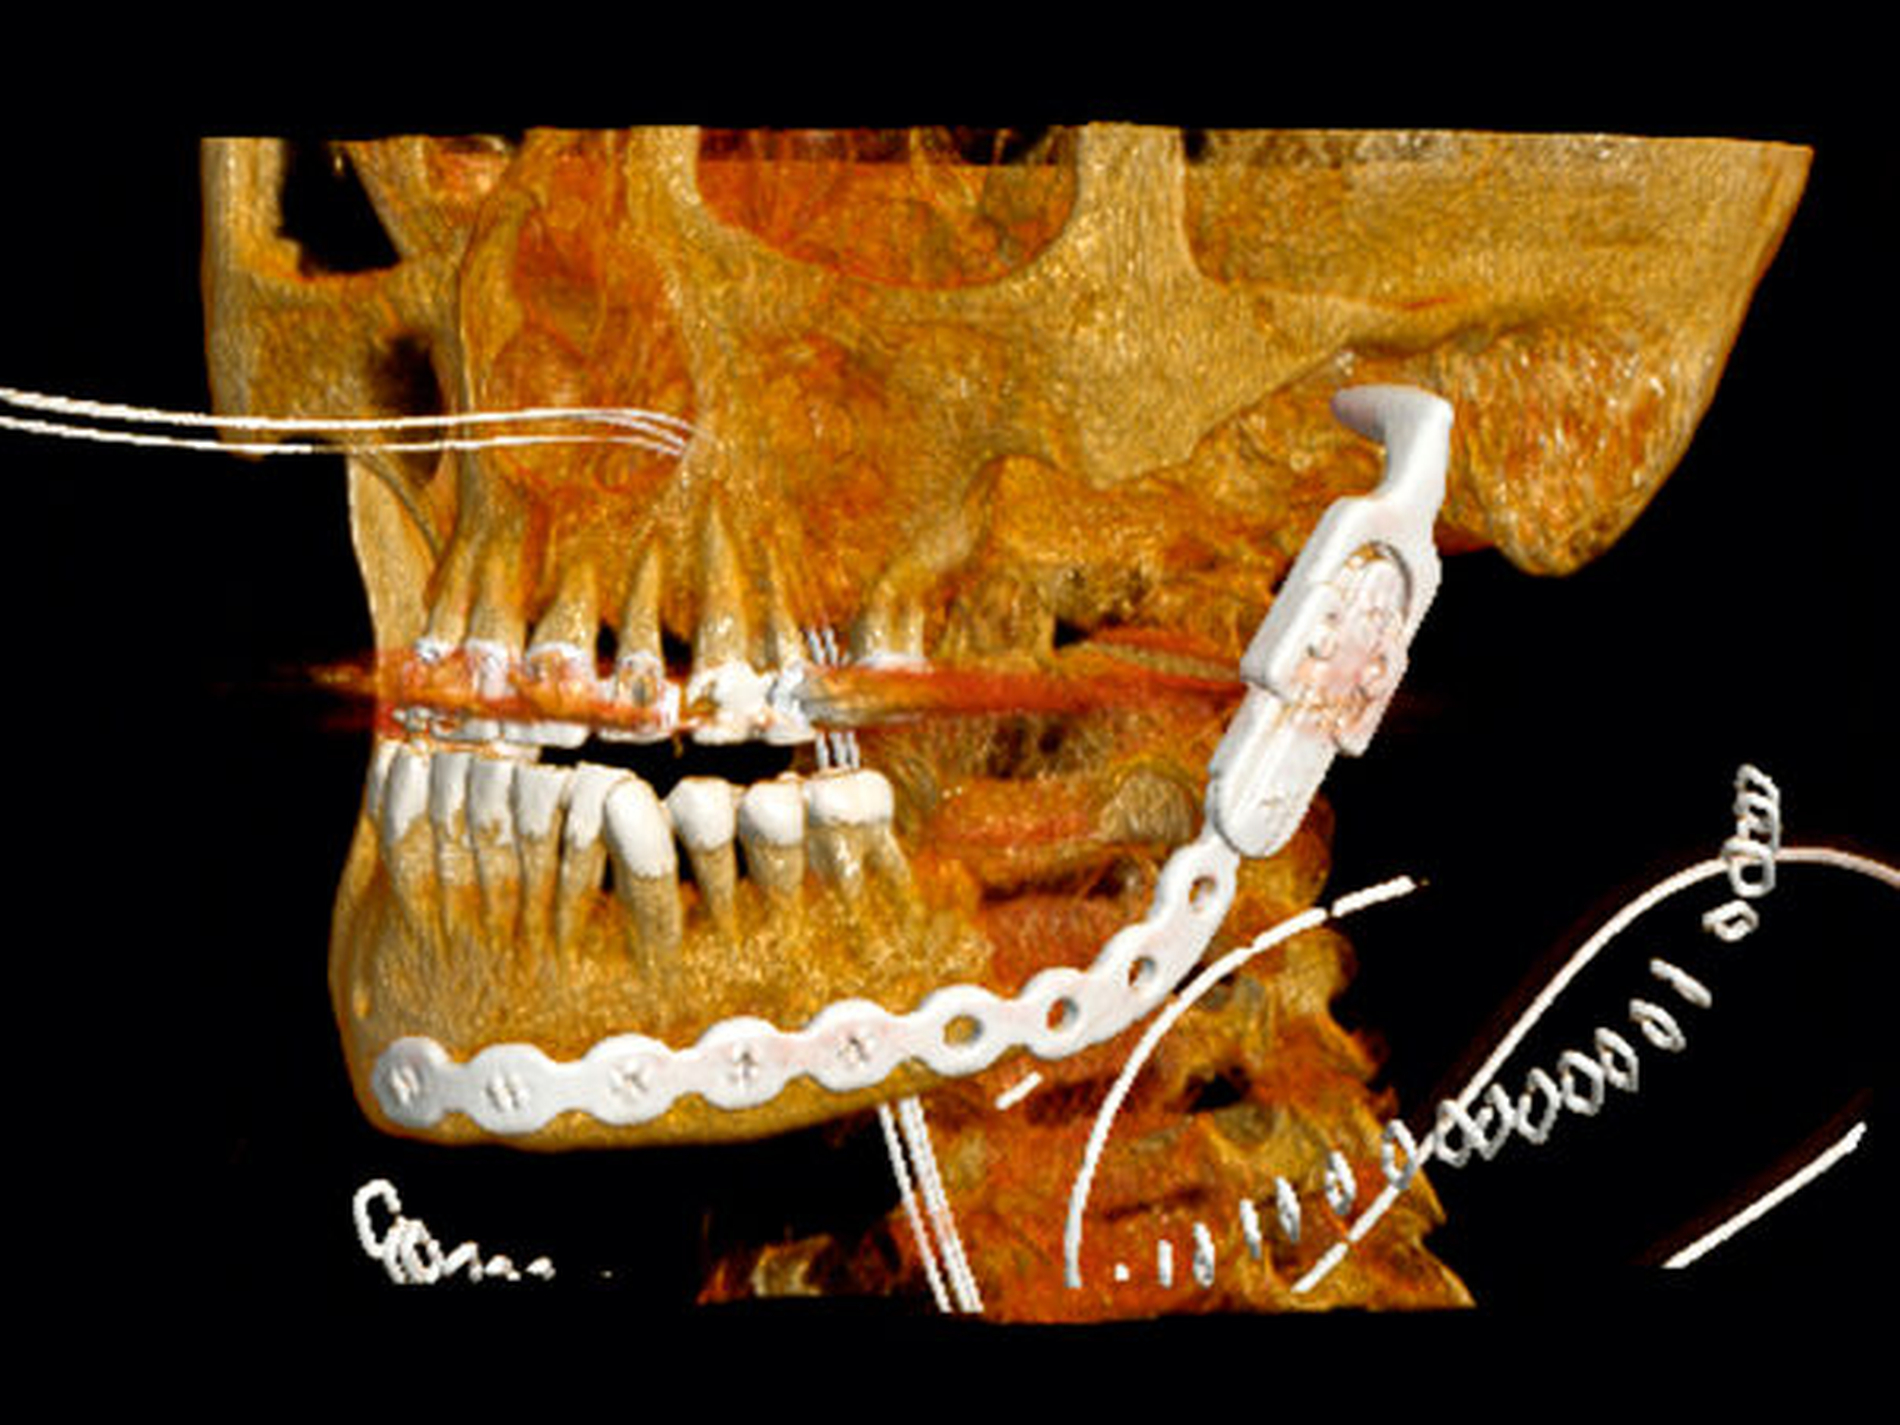

In Vollnarkose erfolgte von extraoral die Einlage eines weiteren Röhrchens in Richtung links submandibulär-anterior sowie eine gründliche Revision der intraoralen Wunden. Dabei kam es bei der intraoralen Inspektion und Wundrevision zu einer pathologischen Kieferwinkelfraktur. Es bestätigte sich die bereits in der CT-Bildgebung diagnostizierte, ausgeprägte osteolytische Veränderung des Unterkieferknochens. Die Fraktur wurde zunächst temporär mittels einer 2.0-Mini-Osteosyntheseplatte fixiert (Abbildung 3).

Aufgrund des ausgedehnten Befunds fiel die Entscheidung zu einer Kontinuitätsresektion mit einer Exartikulation des linken Kiefergelenks und Einbringen einer Rekonstruktionsplatte mit Gelenkersatz (Abbildung 4). Der N. alveolaris inferior sowie der N. lingualis konnten erhalten werden. Die pathologische Aufarbeitung des Unterkieferresektats zeigte eine umschriebene Knochennekrose mit mehrherdiger, überwiegend chronischer Osteomyelitis zusammen mit einer Fettmarksfibrose und einer periostalen Stromafibrose.